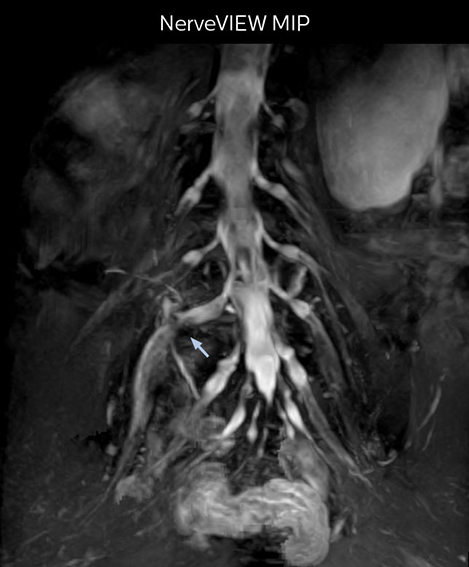

“In such case, we would then browse through axial T2-weighted MR images slice by slice and mentally reconstruct the actual situation based on both radiculography and MRI. Fortunately, NerveVIEW can now very well show nerve courses and presence of nerve compression or edema in one single image series.” “We have often seen NerveVIEW directly depict details of the nerve compression that were not observed by radiculography. Therefore, we think that with NerveVIEW we can reduce the number of invasive examinations, especially for some patients with lumbar plexus symptoms.”

“Before NerveVIEW, diagnosis by MRI alone was sometimes difficult, unless there was a strong suspicion based on clinical symptoms,” says Shoji Yabuki, MD, DMSc, Orthopedic surgeon at Fukushima Medical University School of Medicine. “This is why we routinely perform selective lumbosacral radiculography (nerve root block) and x-ray in such cases. However, radiculography can only depict nerves as far as the contrast agent reaches. When a nerve is distorted by compression, the contrast agent will not pass through this compressed area, preventing us from evaluating the full nerve compression.”

The key concept in MR neurography, Dr. Yabuki stresses, is the ability to directly visualize spinal nerves, versus inferring the presence of pathology indirectly. “Before NerveVIEW, we estimated compression of the nerve by looking for the presence or absence of fat signal on other MR images,” he says.

“For example, in sagittal images, when the presence of fat is observed in the intervertebral foramen, it suggests that there is a margin around the nerve. Similarly, the absence of fat indicates that the nerve is being compressed. So, we used to deduce nerve compression indirectly. With NerveVIEW, however, we can observe the condition of the nerves directly, regardless of the presence or absence of fat. We always prefer such direct observation of anatomy over having to make an inference about it.”